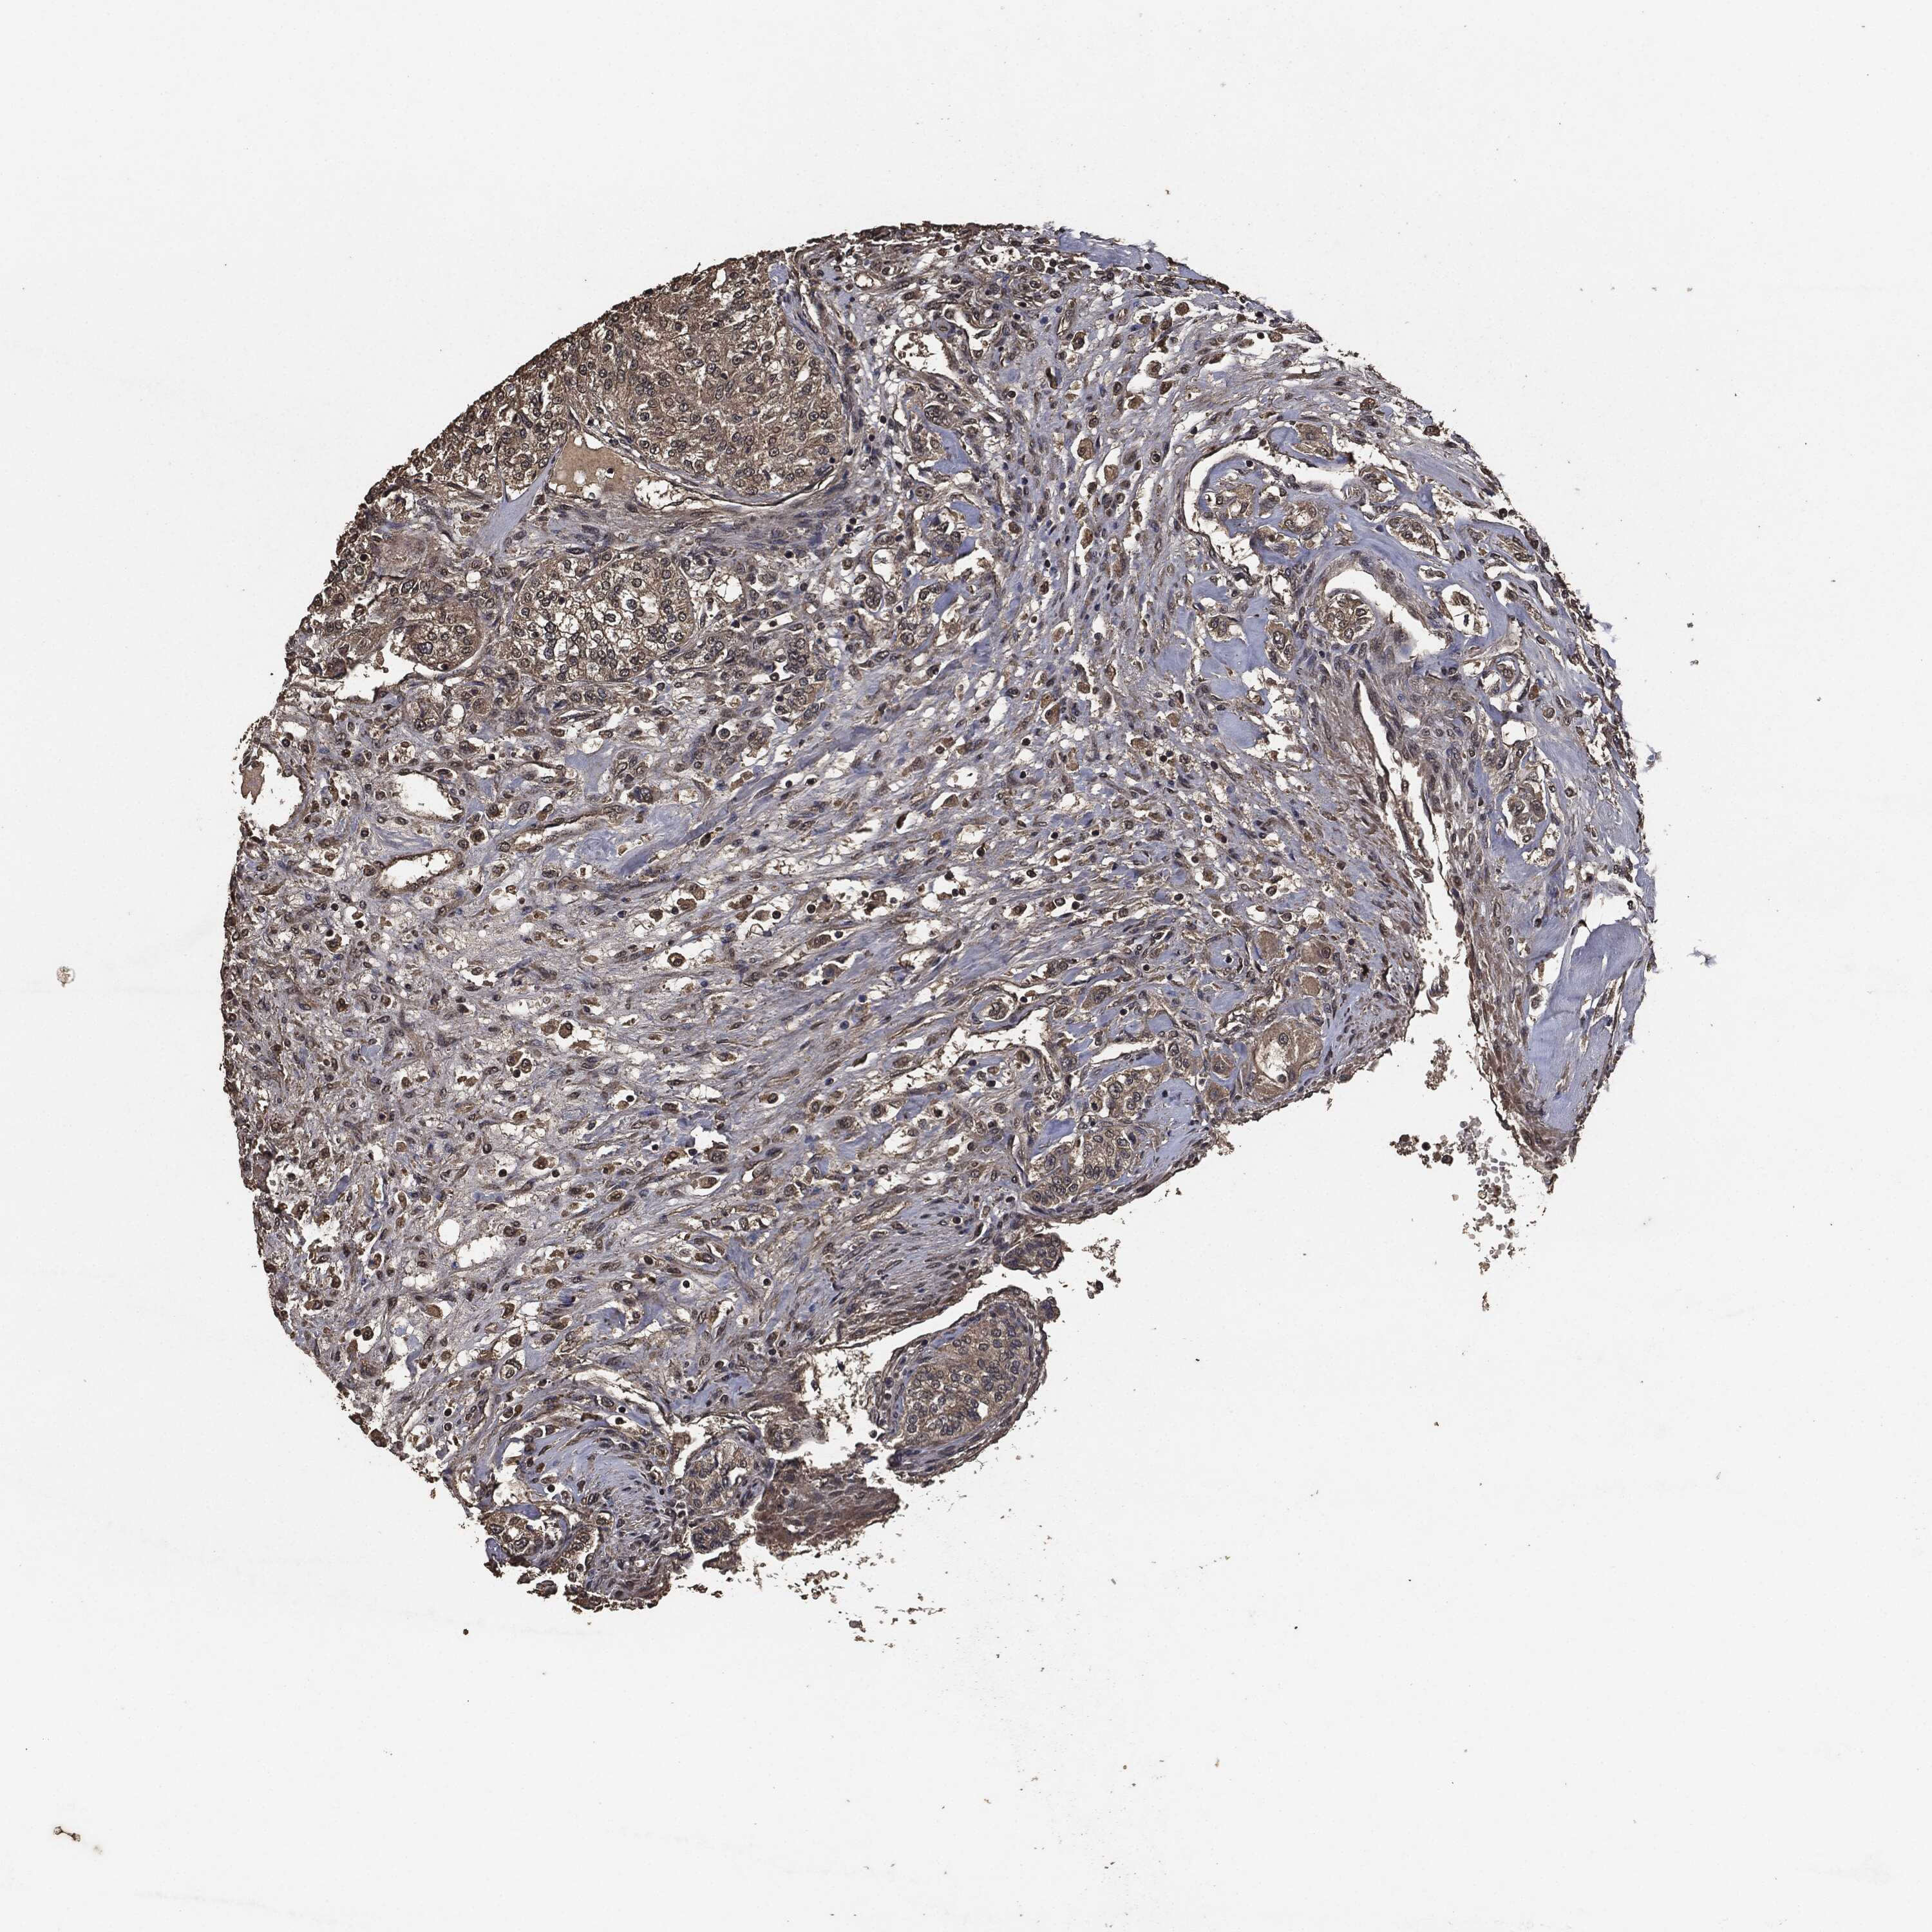

KIDNEY RENAL CLEAR CELL CARCINOMA (VALIDATION) - Interactive survival scatter ploti

The Survival Scatter plot shows the clinical status (i.e. dead or alive) for all individuals in the patient cohort, based on the same data that underlies the corresponding Kaplan-Meier plots. Patients that are alive at last time for follow-up are shown in blue and patients who have died during the study are shown in red.

The x-axis shows the expression levels (FPKM) of the investigated gene in the tumor tissue at the time of diagnosis. The y-axis shows the follow-up time after diagnosis (years). Both axes are complimented with kernel density curves demonstrating the data density over the axes. The top density plot shows the expression levels (FPKM) distribution among dead (red) and alive patients (blue). The right density plot shows the data density of the survived years of dead patients with high and low expression levels respectively, stratified using the cutoff indicated by the vertical dashed line through the Survival Scatter plot. This cutoff is automatically defined based on the FPKM cutoff that minimizes the p-score. The cutoff can be changed by dragging the vertical line or by entering a cutoff value in the square labeled "Current cut-off".

Under the Survival Scatter plot the p-score landscape (black curve; left axis) is shown together with dead median separation (red curve; right axis). Dead median separation is the difference in median mRNA expression between patients who have died with high and low expression, respectively. It is calculated as follows: median FPKM expression of dead patients with high expression - median FPKM expression of dead patients with low expression. This is intended to aid the user in visually exploring custom cutoffs and the associated p-scores and dead median separation.

Individual patient data is displayed and can be filtered by clicking on one or more of the category buttons on the top of the page. Categories describing expression level and patient information include: high, low, alive, dead, female, male and tumor stages. The scale of the x-axis can be toggled between linear and log-scale by clicking on the "x log" button. Mouse-over function shows TCGA ID, patient information and mRNA expression (FPKM) for each patient.

& Survival analysisi

Kaplan-Meier plots summarize results from analysis of correlation between mRNA expression level and patient survival. Patients were divided based on level of expression into one of the two groups "low" (under cut off) or "high" (over cut off). X-axis shows time for survival (years) and y-axis shows the probability of survival, where 1.0 corresponds to 100 percent.

AKT1S1 is not prognostic in Kidney Renal Clear Cell Carcinoma (validation)

Best expression cut offi

Based on the FPKM value of each gene, patients were classified into two groups and association between prognosis (survival) and gene expression (FPKM) was examined. The best expression cut-off refers the FPKM value that yields maximal difference with regard to survival between the two groups at the lowest log-rank P-value. Best expression cut-off was selected based on survival analysis .

When clicking on this number, the vertical dashed line indicating cut-off, the interactive survival plot, and the Kaplan-Meier curve will be adjusted to show results based on the best expression cut-off.

: 50.34

P scorei

Log-rank P value for Kaplan-Meier plot showing results from analysis of correlation between mRNA expression level and patient survival.

N/A

TCGA RNA samplesi

RNA-seq data is reported as average FPKM (number Fragments Per Kilobase of exon per Million reads), generated by the The Cancer Genome Atlas (TCGA) .

Normal distribution across the dataset is visualized with box plots, shown as median and 25th and 75th percentiles. Points are displayed as outliers if they are above or below 1.5 times the interquartile range. FPKM values of the individual samples are presented next to the box plot.

Average pTPM 41.0

Number of samples 100